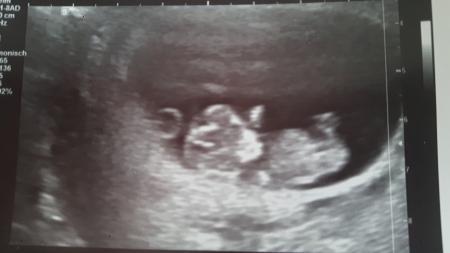

Ich bin such wieder zurück. Dem Krümel-Kind geht's prima. Es hat aber wahrscheinlich geschlafen. Hat sich nämlich nicht bewegt. Aber das Herzchen hat fleißig geblubbert und es ist exakt so groß, wies sein soll. So kann ich nächsten Montag beruhigt mein meiner großen in Mutter-Kind-Kur fahren. Außerdem bin ich ab heute auch schon in der 11. Woche... Nächster Termin ist dann am 20.02.

Bild zu Zurück von Der FÄ - Forum für August - Mamis